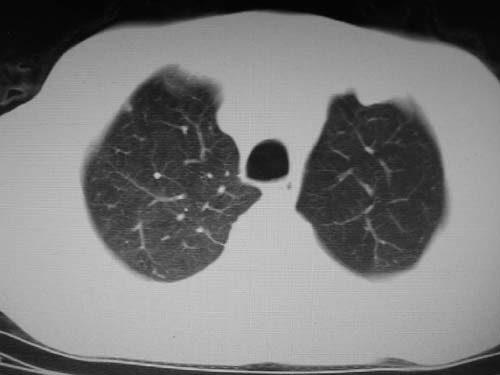

男,80岁

1)考虑肺动脉狭窄。2)右肺上叶继发性肺结核。3)右侧胸膜增厚、钙化,左侧胸膜反应。

左肺动脉异常增粗,建议ct增强,排除肺门肿瘤

右肺上叶继发性肺结核。

右侧胸膜增厚、钙化,左侧胸膜反应

1)考虑左肺动脉瘤可能性大,建议增强。2)右肺上叶继发性肺结核。3)右侧胸膜增厚、钙化,左侧胸膜反应。

)考虑肺动脉扩张,右心室增大,主动脉弓段正常位弓后段明显变小(不会是动脉导客未闭吧,不知患者有何症状病史)0。2)右肺上叶继发性肺结核。3)右侧胸膜增厚、钙化,左侧胸膜反应。

右肺上叶尖段结核;左肺下叶占位?建议增强扫描。右侧胸膜增厚;右肺局限性肺气肿。